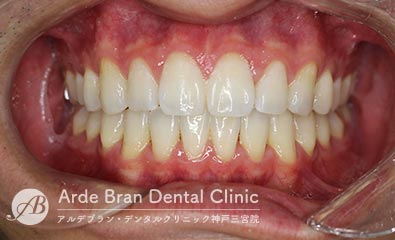

- 叢生/歯のがたつき(20代女性 治療期間6カ月)

- 上の前歯の歯のがたつきを治したいとの事でご来院されました。上の歯のみの部分矯正をご希望され、なるべく目立たない装置で治療を行いたいとの事だったのでインビザラインライトにて治療を行いました。上下でフルの矯正を行うのがベストではありますが、短期間で歯のがたつきが改善され、見た目も大きく改善し非常にご満足頂けました。

- 治療前

- 治療後

| 装置名 | インビザライン(マウスピース矯正) |

| 抜歯非抜歯 | 非抜歯 |

| 治療期間 | 6カ月 |

| 費用 | インビザラインライト(上のみ)35万円+TAX 再印象(3万円+TAX)×1回 |